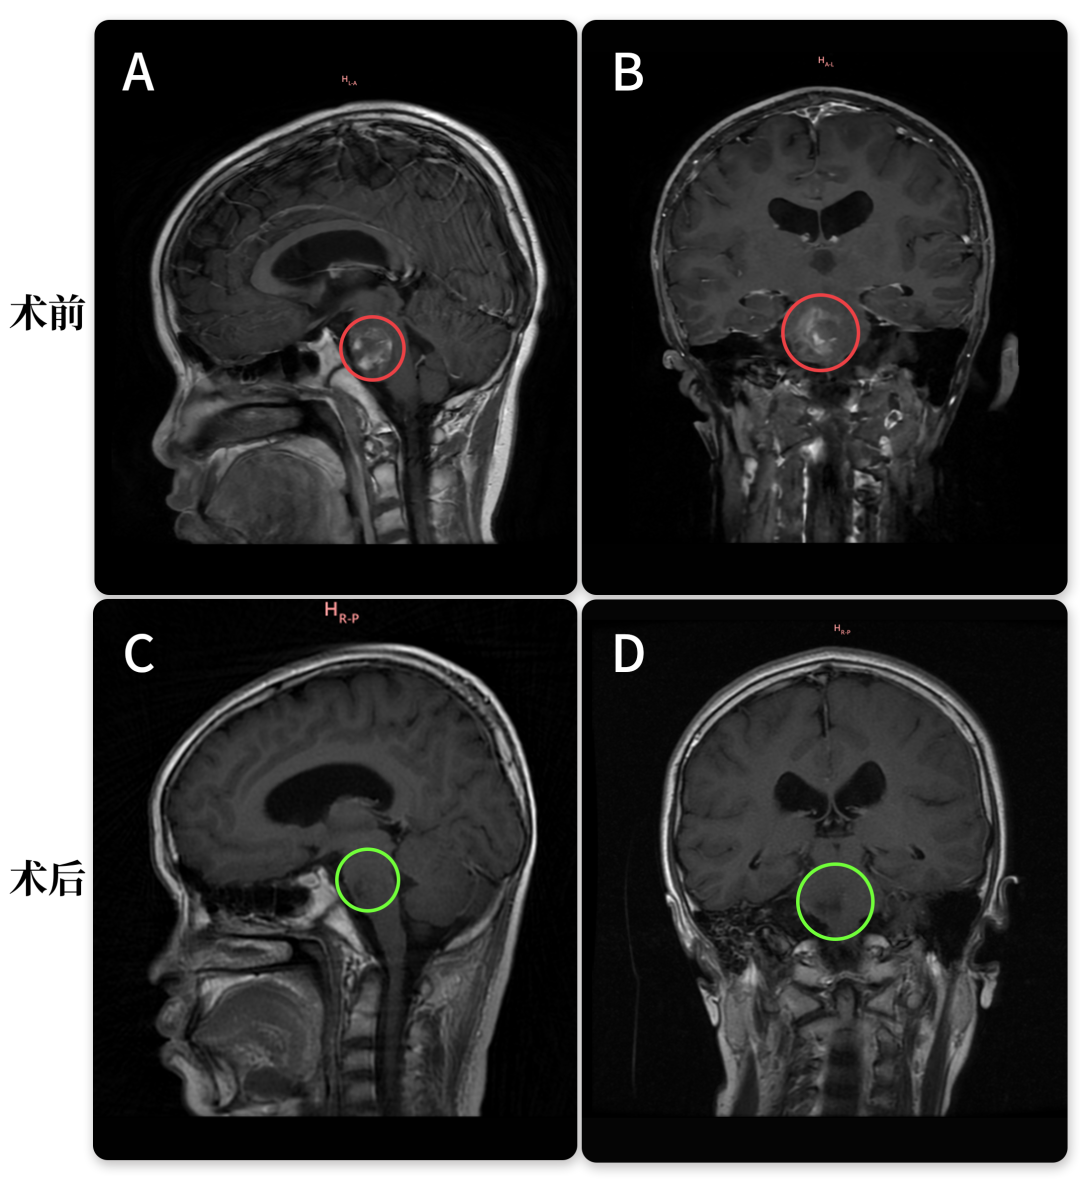

然而,三月后的复查结果一度使全家再度陷入忧虑。MRI报告显示:脑干区域存在异常信号,考虑为海绵状血管瘤可能;同时发现右侧天幕下有一处蛛网膜囊肿。焦虑不已的父母立即联系巴教授,却意外获得教授的乐观回应:无需担忧,这实际上是好消息!

巴教授在远程评估小雨的最新影像后表示:“好消息!患儿临床状态良好,这与MRI结果相符。”又三个月后,得知巴教授即将来华,小雨母亲特意带孩子前往苏州,一方面为当面致谢,另一方面也希望教授亲自评估孩子状况。此次,巴教授给出了更详细的解释:报告中所谓的“异常信号”并非肿瘤残留,而是含铁血黄素沉积,这对于像小雨这样曾罹患巨大出血性脑干病变的患者属于正常现象,并不代表存在活跃的海绵状血管瘤。此外,针对蛛网膜囊肿,巴教授宽慰道:“若无症状,无需任何治疗,不必过分担心。”教授肯定而自信的回答,终于让小雨全家放下心中重石。

尽管之后小雨一家成功邀请巴教授完成海绵状血管瘤全切手术,但此前两次脑干出血已为本次MRI显示的“异常信号”埋下伏笔。

需知的是,脑干海绵状血管瘤易出现反复微量出血,当脑组织存在慢性出血或血管损伤时,其代谢产物可导致含铁血黄素沉积。这类沉积并非疾病状态,正如巴教授所言,对于像小雨这样接受巨大海绵状血管瘤全切除的病例,属正常术后表现。